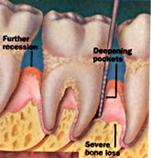

Parodontite severe

mobilitate dentara accentuata pâna la avulsia dintilor

migrari patologice

halena constanta

hiperestezie dentinara datorata denudarii radacinii

pungi parodontale > de 6 mm

resorbtie osoasa accentuata